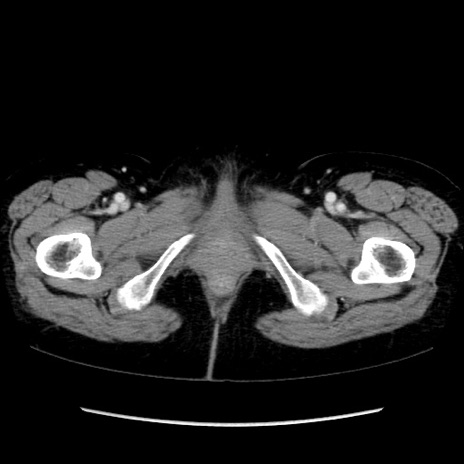

症例32(横断像)

【症例】40歳代 女性

【既往歴】子宮頚癌(広汎子宮全摘術、放射線療法)、腸閉塞